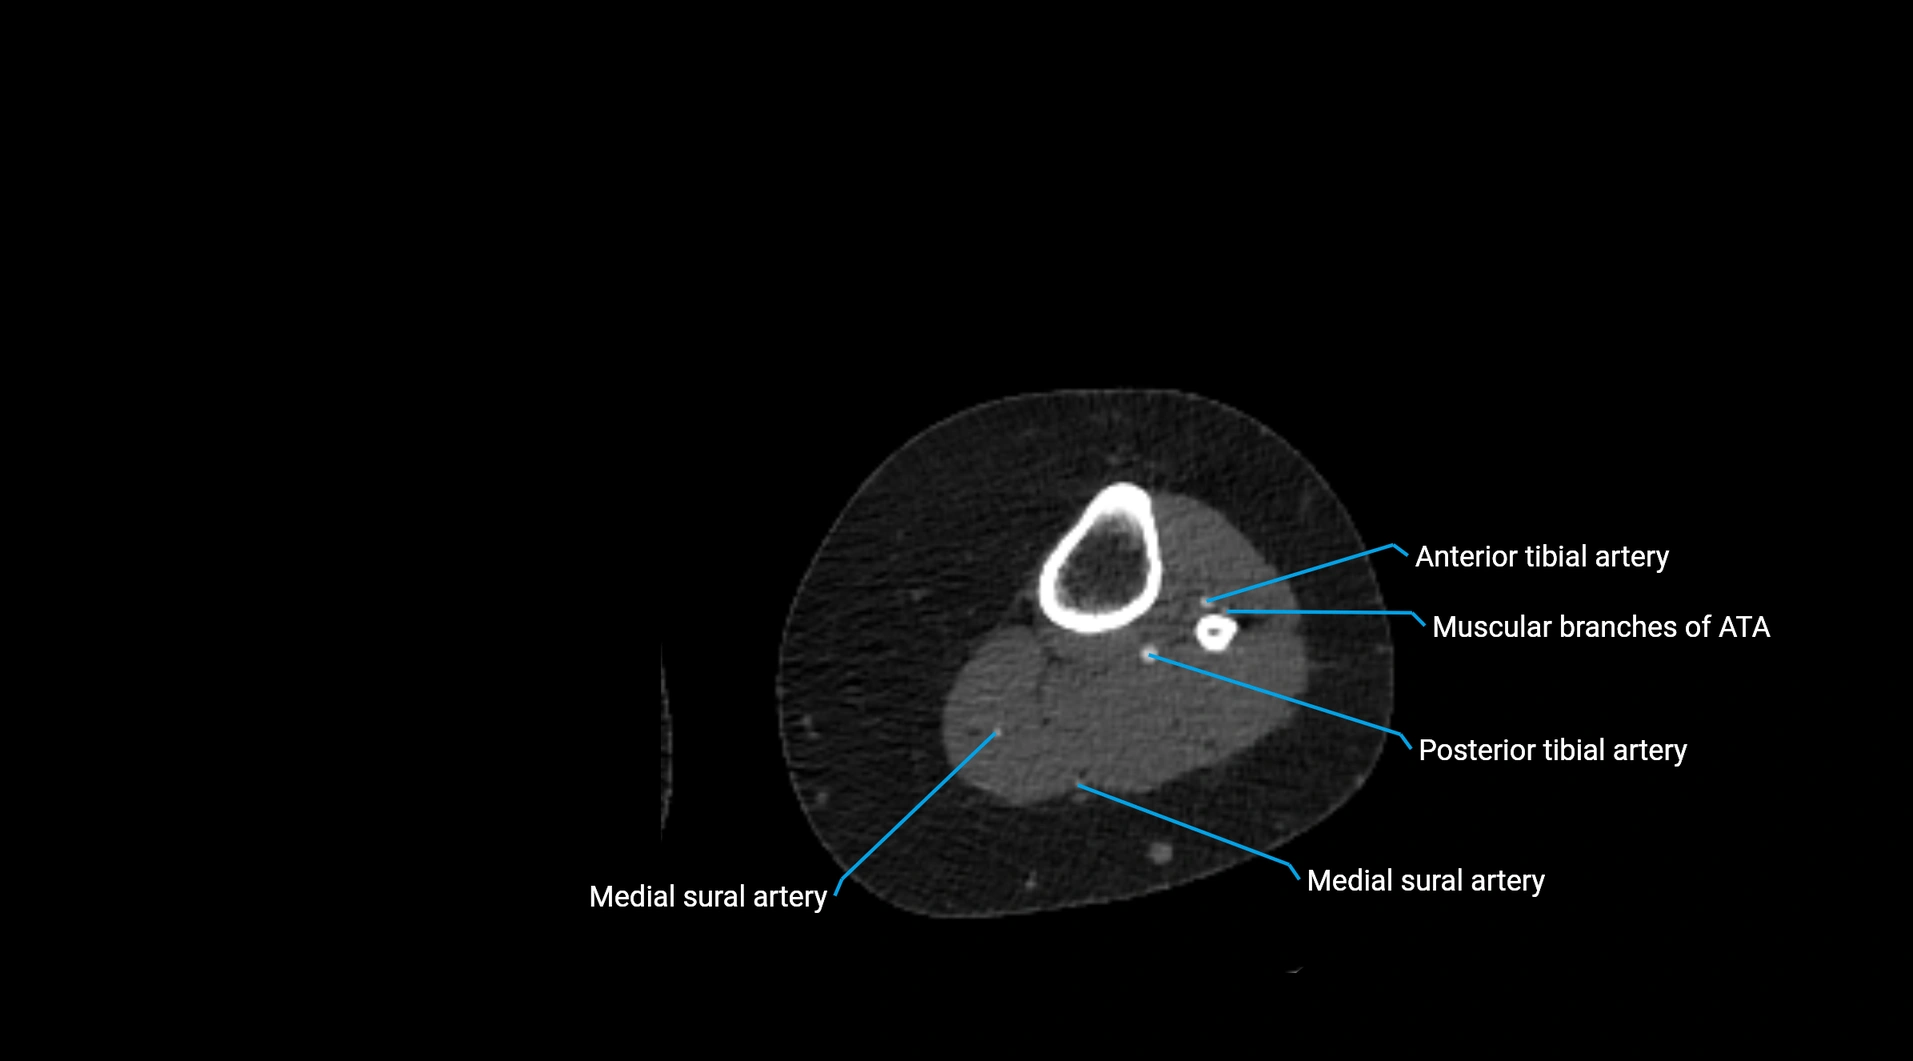

Contrast-enhanced CT (CTA):

• Gold standard for abdominal aortic imaging

• Provides excellent detail of lumen, wall, aneurysm, thrombus, and branch vessels

• Multiplanar and 3D reconstructions help in aneurysm measurement, stent graft planning, and dissection evaluation